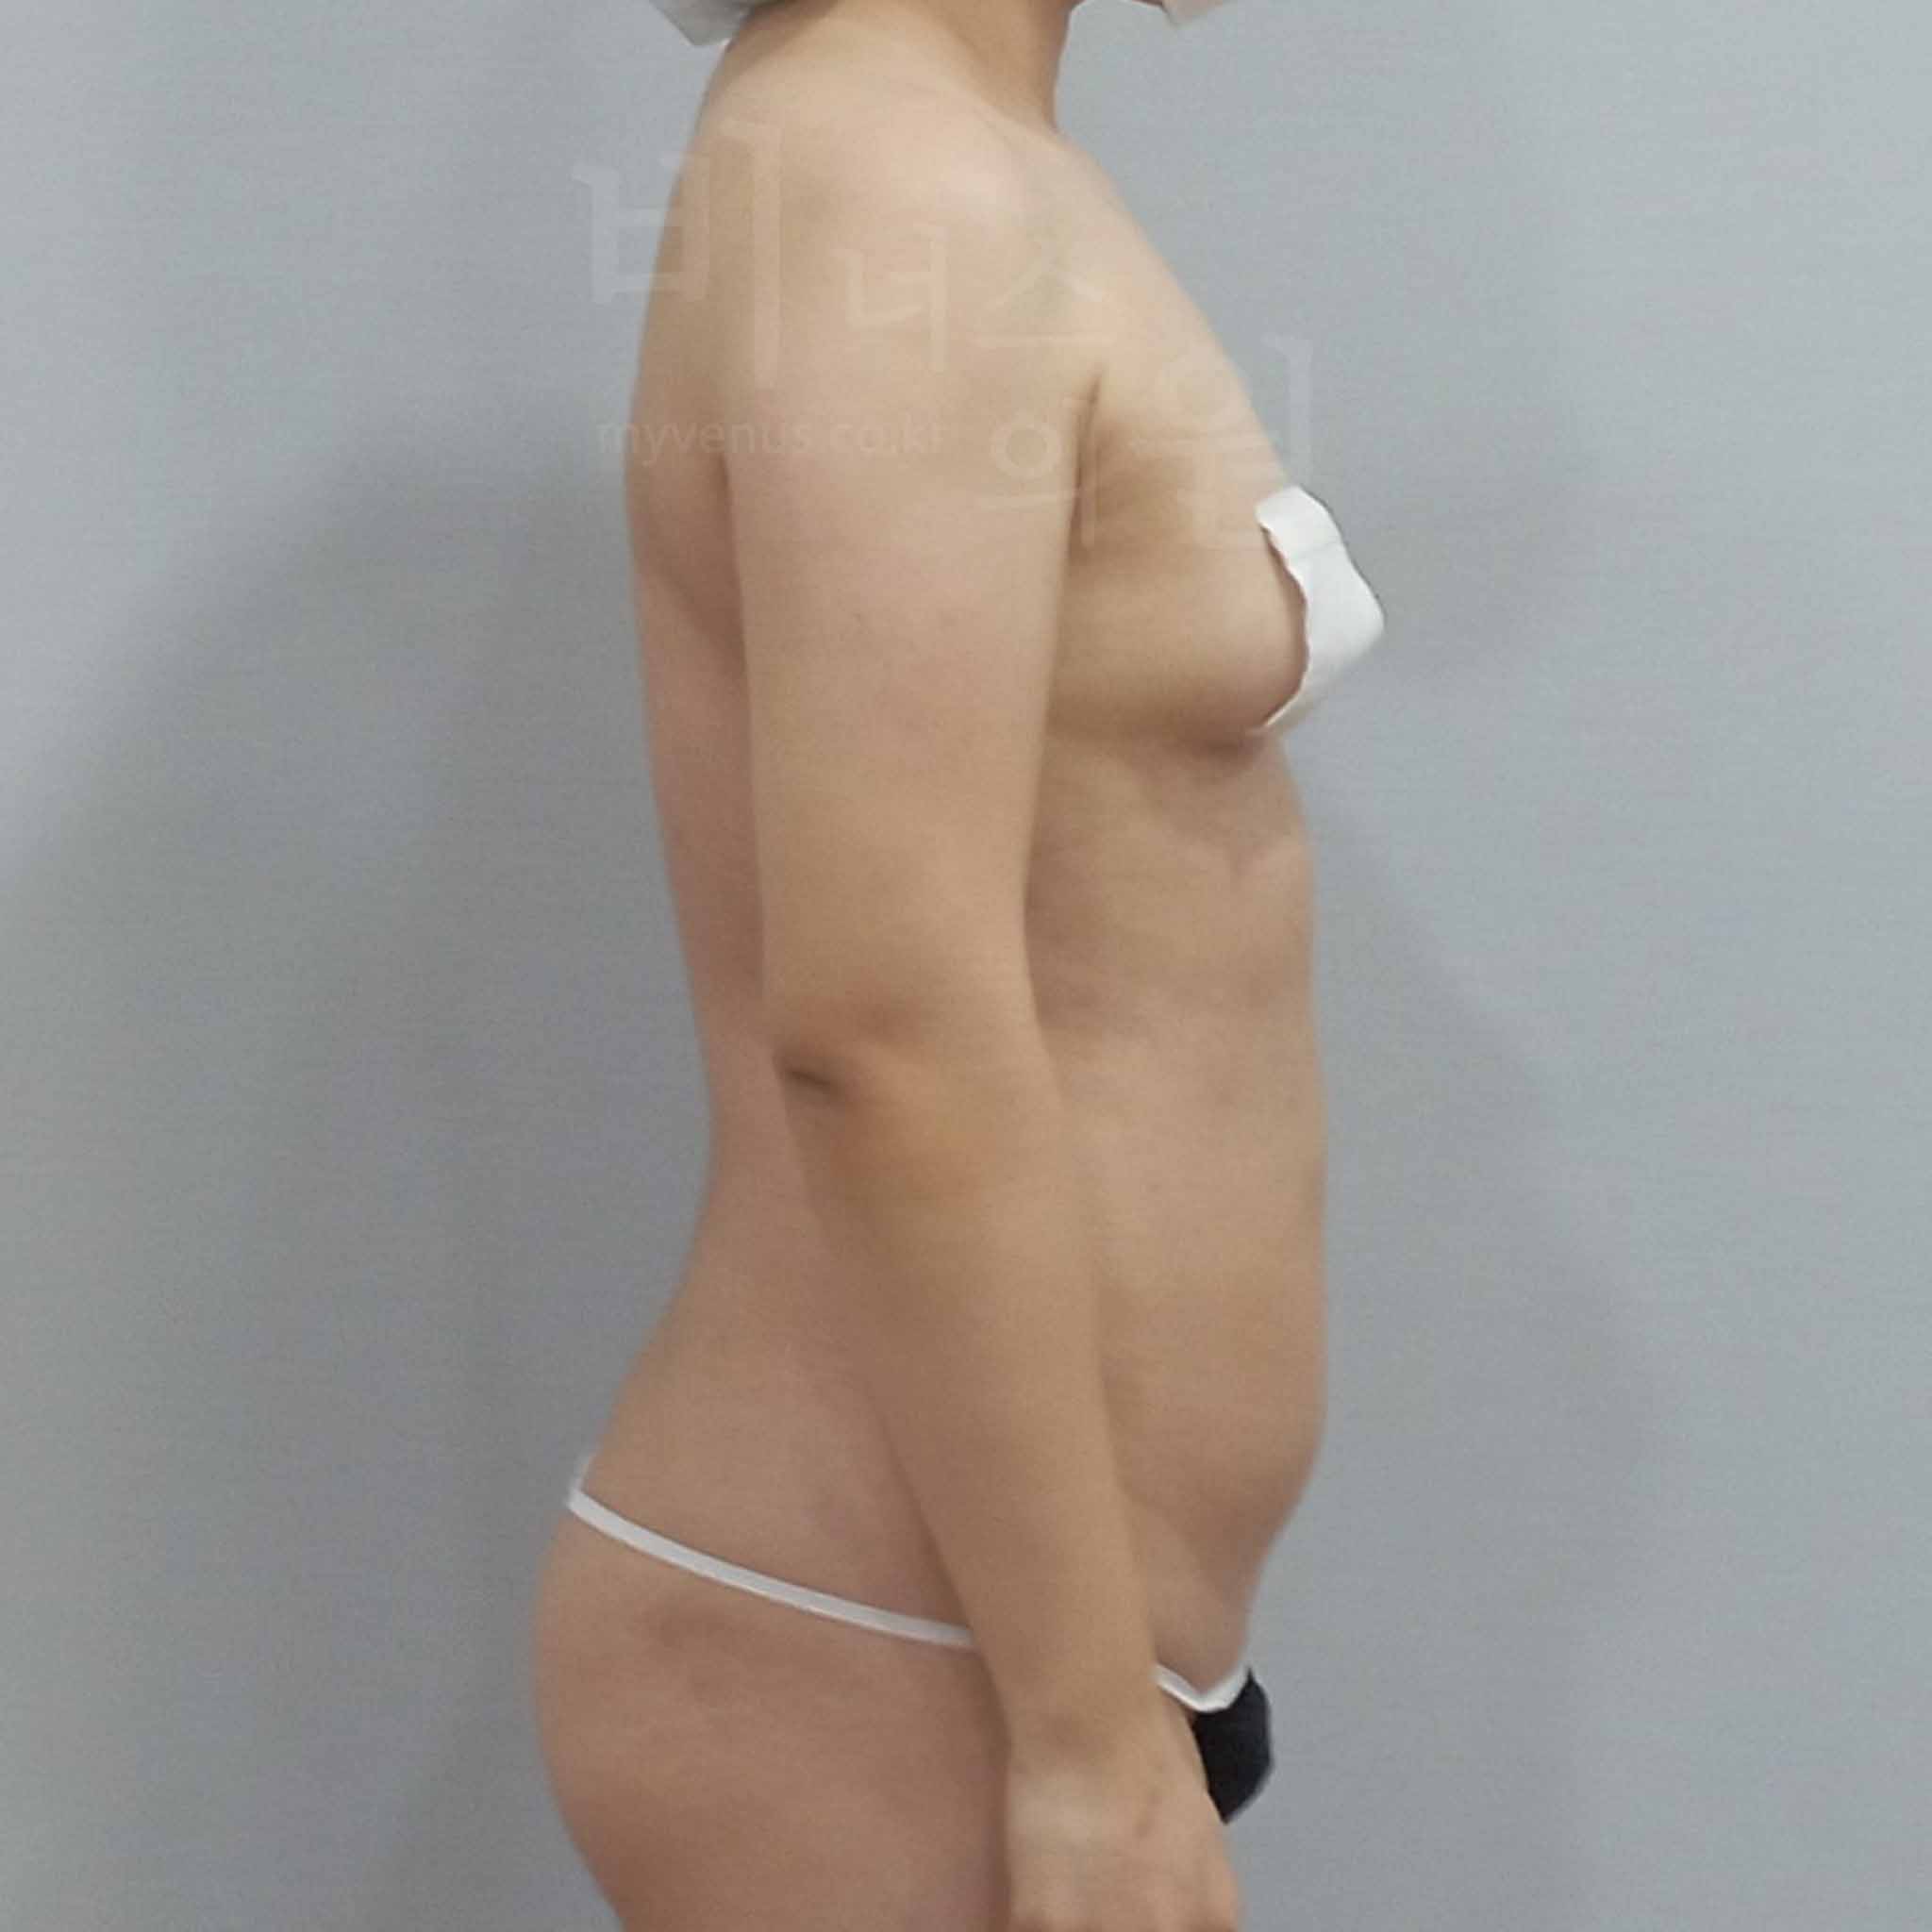

아래 사진은 수술 당일과 수술 후 1주일 경과 시기의 모습으로, 멍과 부기가 남아 있을 수 있는 회복 초기 단계의 과정입니다. 회복 속도와 멍 정도는 개인차가 있을 수 있지만, 대부분은 일상생활에는 무리가 없으며, 팔뚝의 변화는 1개월, 3개월, 6개월에 걸쳐 점진적으로 개선이 됩니다.

연령대 - 50대 중반

경과 기간 - 일주일 경과

수술 부위 - 팔꿈치 포함 원통형 팔뚝, 앞 겨드랑이, 뒷 겨드랑이, 부유방 지방흡입

팔뚝 지방흡입 전 사진

출렁이고 탄력 없는 팔뚝 살

팔뚝 지방흡입 후 사진

처짐 없이 슬림해진 팔뚝 라인

수술 전 - 팔뚝 하방의 지방 축적으로 인해 전체적으로 굵고, 피부가 아래로 처져 보여 팔을 드는 것조차 부담이었던 상태였습니다.

수술 후 - 핸드 리프팅 지방흡입으로 피부 처짐 없이 자연스럽고 균일한 사이즈 감소가 이루어졌고, 팔 라인이 정돈되며 탄력 있는 인상으로 변화되었습니다.

연령대 - 40대 후반

경과 기간 - 일주일 경과

수술 부위 - 팔꿈치 포함 원통형 팔뚝, 앞 겨드랑이, 뒷 겨드랑이, 부유방 지방흡입

팔뚝 지방흡입 전 사진

팔 아래 출렁이는 팔뚝 살

팔뚝 지방흡입 후 사진

탄력 있고 슬림해진 팔뚝 살

수술 전 - 운동으로도 빠지지 않는 팔뚝살과 팔 아래 출렁이는 늘어진 피부로 스트레스를 받으셨으며, 팔꿈치 포함 전체 팔뚝과 앞·뒤 겨드랑이의 군살이 고민이었습니다.

수술 후 - 팔뚝 전체와 겨드랑이 부위까지 균일하게 지방이 제거되며 눈에 띄는 사이즈 감소와 함께 피부의 탄력도 함께 회복되어 더욱 매끄럽고 자연스러운 팔 라인으로 개선되었습니다.